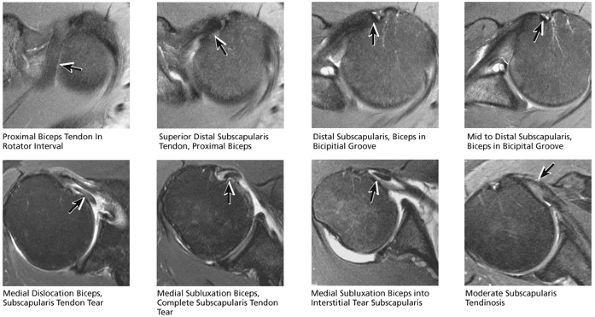

FIGURE 8.30 ● Axial images through the AC joint should be obtained on all shoulder MR examinations. (A) Axial T1- or PD-weighted images at this location are used to identify fractures of the distal clavicle and to demonstrate an os acromiale. (B) Axial FS PD-weighted images show cartilage covering the distal aspect of the clavicle and the medial aspect of the acromion at the AC joint. Cartilage defects and thinning, as well as subchondral bone marrow edema and cystic change, are evaluated on axial images through the AC joint. These degenerative changes can mimic the symptoms of a rotator cuff tear. (C) Axial T1- or PD-weighted images demonstrate the Hill-Sachs lesion of the humeral head, usually visualized as focal flattening or concave deformities in the posterolateral humeral head. The Hill-Sachs lesions is identified on the first or second superior axial image through the humeral head. Subcortical cystic change is more commonly visualized in the posterolateral humeral head and is usually an incidental finding in asymptomatic patients. (D) Axial FS PD-weighted images depict the biceps tendon coursing across the anteromedial aspect of the humeral head, within the rotator interval. This image location serves as a starting point for following the remainder of the biceps tendon into the bicipital groove on successive axial images moving from cranial to caudal. Tears of the supraspinatus and infraspinatus tendons are also identified at this image location on axial images. (E) Axial T1- or PD-weighted images allow evaluation of subcoracoid impingement. (F) In this location, thickening and increased signal in the superior glenohumeral ligament and coracohumeral ligament on an axial FS PD-weighted image may indicate adhesive capsulitis, particularly when accompanied by thickening and increased signal within the inferior glenohumeral ligament. (G) Axial T1- or PD-weighted images are used to identify subcortical cystic change in the greater and lesser tuberosity. This finding is commonly an indirect indication of abnormality or tearing in the overlying distal supraspinatus and subscapularis tendons, respectively. (H) Axial FS PD-weighted images through the proximal bicipital groove are used to identify “hidden lesions,” which are diagnosed when the biceps tendon is medially subluxing out of the bicipital groove, usually into a distal subscapularis tear or anterior to the lesser tuberosity. A degenerated biceps tendon may appear flattened and elongated as it rounds the lesser tuberosity into the proximal bicipital groove. Commonly, only the medial “tail” of the flattened degenerated biceps tendon subluxes out of the groove; the remainder of the flattened biceps tendon stays within the groove. (I) Axial T1- or PD-weighted images display the osseous glenoid subchondral surface, which should appear flat. Osseous glenoid remodeling, hypertrophy, deformity, subchondral cystic change, and edema are commonly identified as indirect evidence of overlying chronic cartilage degeneration or prior trauma. Posterior glenoid spurring may completely replace a degenerated or markedly attenuated posterior labrum. (J) Axial FS PD-weighted images are optimal for displaying the glenoid and humeral head cartilage. Chondral fissures, thinning, and defects are visualized when viewing successive cranial-to-caudal images through the glenohumeral joint. The anterior and posterior labrum are also optimally visualized and are normally firmly adherent to the glenoid and glenoid articular cartilage. (K) Axial T1- or PD-weighted images are used to identify bony Bankart lesions. These lesions are seen on inferior axial images through the glenohumeral ligament as oblique fracture lines extending through the anterior inferior glenoid. (L) Axial FS PD-weighted images show the prominent anterior band of the IGHL, which is occasionally mistaken for a tear of the anterior inferior labrum when fluid is interposed between the anterior band and the normal labrum.